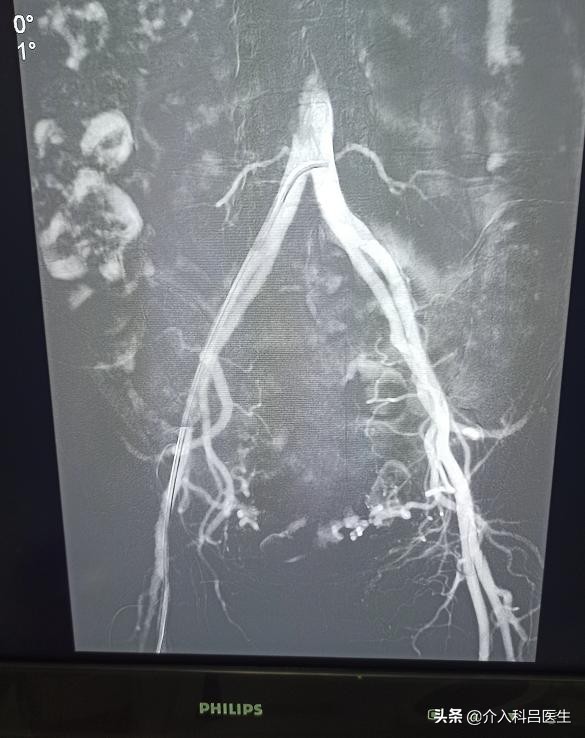

该治疗只需要在患者一侧的大腿根部用细针穿刺,仅有一个 2 毫米的针眼,并不需要进行全麻和开腹。将导管送到子宫肌瘤的供血动脉,推注尽可能小的颗粒型栓塞剂栓塞肌瘤,以阻断肌瘤的病理血管床,使其缺血坏死萎缩,达到“饿死”肌瘤的目的,既可使子宫肌瘤缩小或消失,又可保全子宫功能。介入治疗是在局部麻醉下完成的,手术时无痛苦。术后即可进食,6 小时~8 小时便可自由活动,3 天~5 天就可以出院,休息 7 天~10 天,能正常工作生活。

子宫肌瘤的介入治疗开展30 多年来,积累了大量病例并进行了系统的基础与临床应用研究。长期临床观察发现,介入治疗对各种类型、不同大小、分布不同区域的子宫肌瘤均有效。介入治疗的疗效良好,肌瘤总的缩小率达 80%,其中黏膜下子宫肌瘤高达 100%,肌壁间肌瘤可达 91%。近 20 年来,郑州大学第一附属医院介入科对近 2000 例子宫肌瘤患者经介入治疗后观察,介入对子宫肌瘤引起的月经增多、贫血等具有很好的疗效。